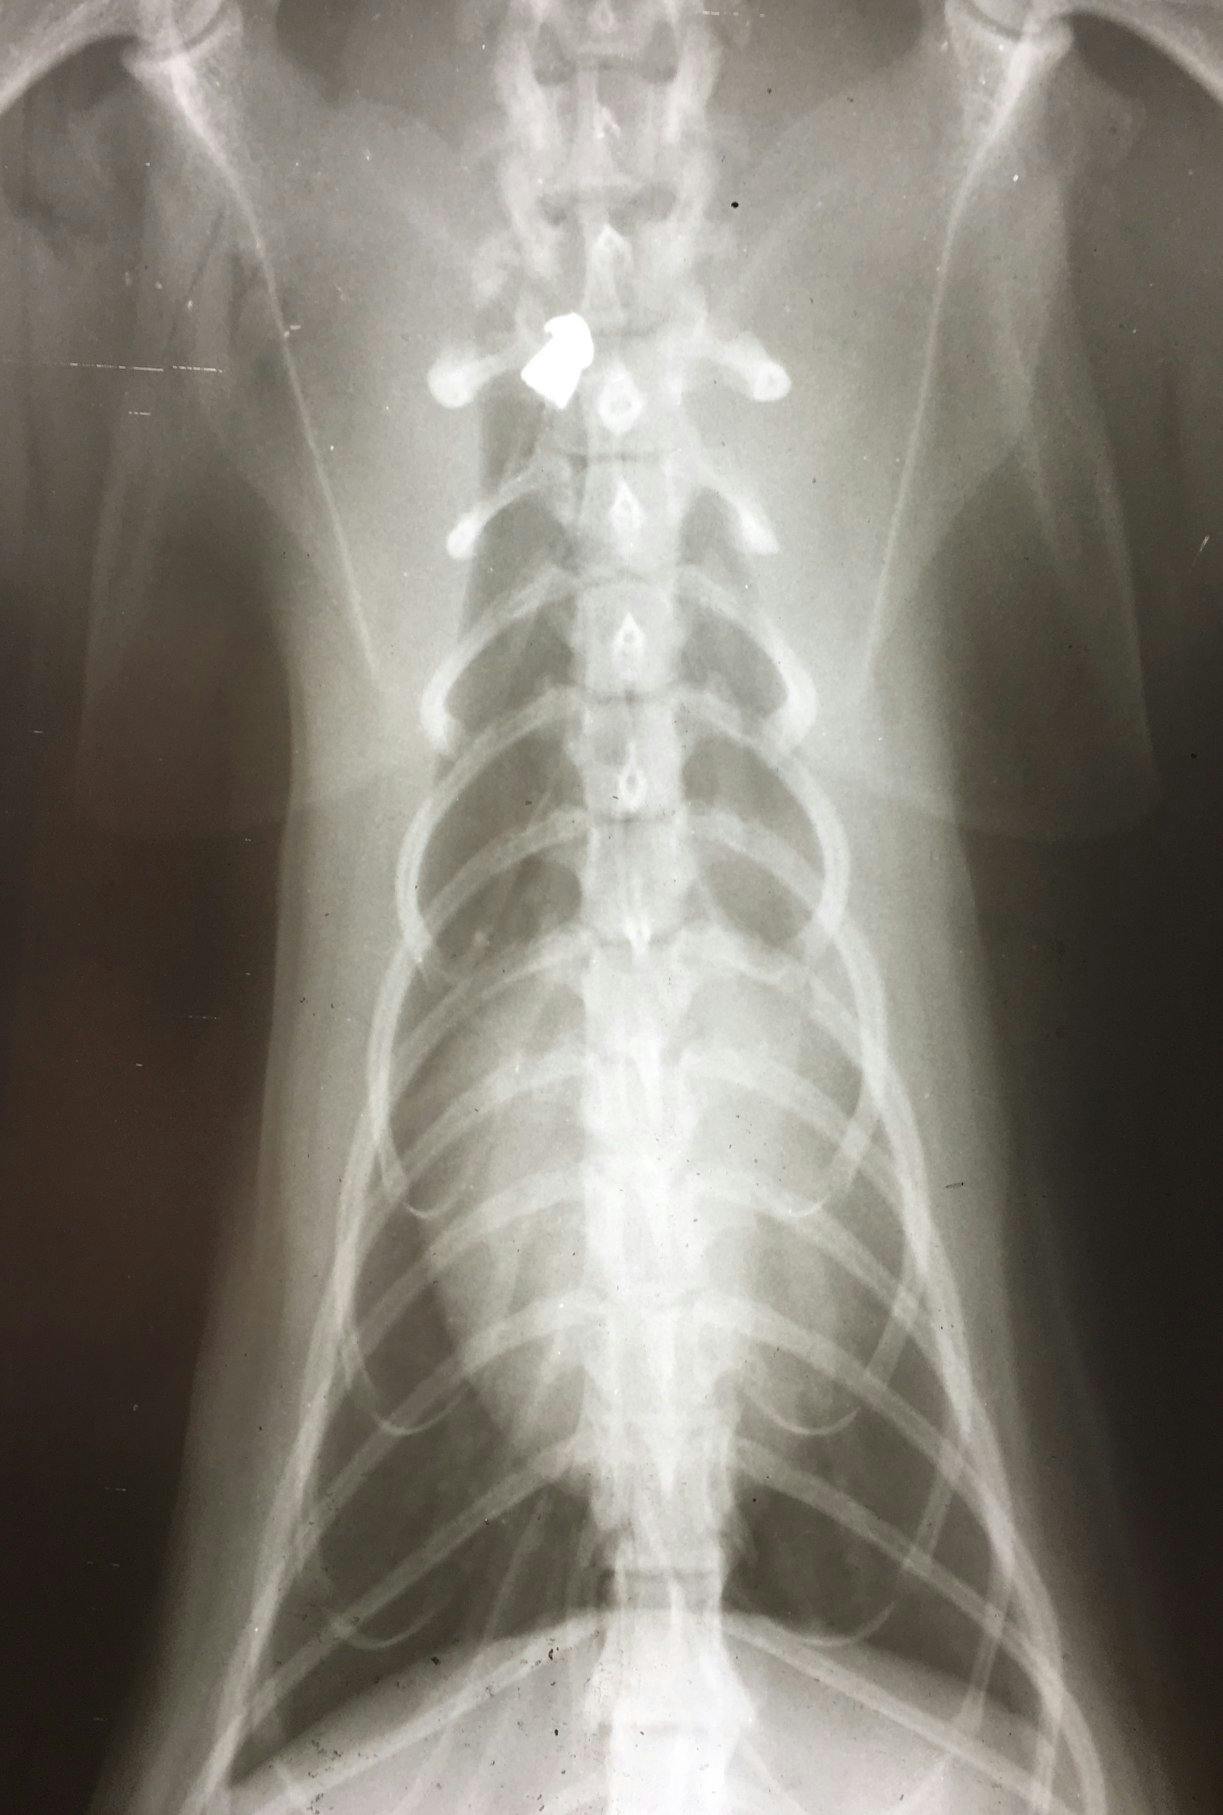

- Kattens ejer troede den var blevet bidt, men nej - på røntgenbilledet, som vi har vedhæftet, ser man tydeligt et hagl mellem rygraden og skulderbladet. Efter en lang operation ligger den søde kat nu på opvågningsstuen, skriver Greve Dyrehospital på deres Facebook-side.

- Haglet lå helt inde ved ryggraden, så det gør situationen lidt anderledes. Men heldigt nok har haglene ramt noget knoglefrembrud, som har 'bouncet' de her fragmenter rundt, så de ikke er gået direkte igennem. Men den havde meget ondt, siger dyrelægen til den lokale tv-station.

- Det er sket inden for de sidste par måneder, og det er alle blevet skudt med et kaliber 45 haglgevær, kan vi se på de hagl, de har haft i kroppen, siger han videre.